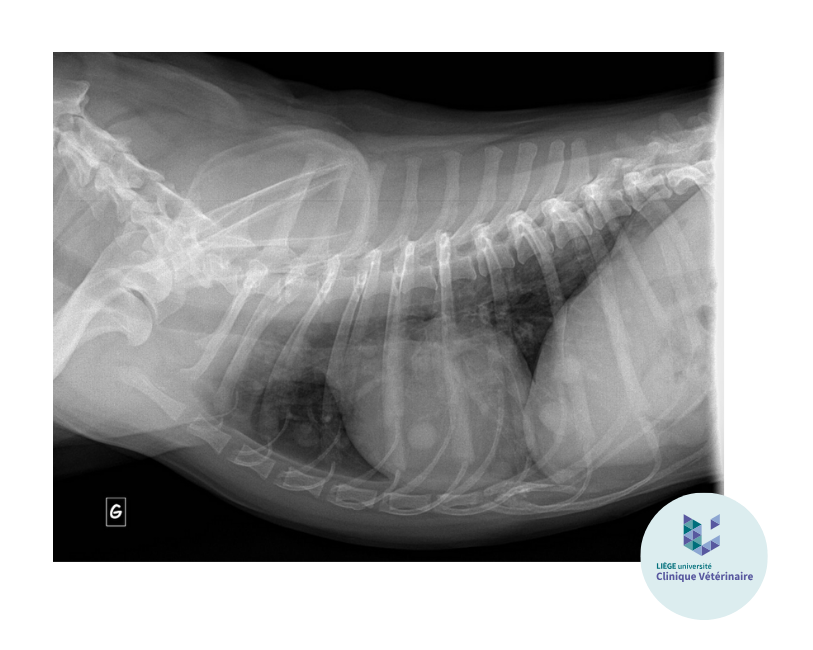

Il se caractérise par la présence de sang, de transsudat, d’exsudat, de cellules ou encore de minéralisations au niveau du tissu interstitiel qui pour rappel entoure les vaisseaux sanguins et lymphatiques, les bronches et les alvéoles. L’opacification du tissu interstitiel apparaît alors comme un « voile grisé » sur le champ pulmonaire. Le poumon paraît plus blanc mais contrairement au pattern alvéolaire les marges des vaisseaux pulmonaires restent visibles même si ceux-ci apparaissent flous et mal délimités. Vous pouvez retrouver ce pattern par exemple lors de fibrose, obésité, pneumonie, œdème allergique, hémorragie ou néoplasie.